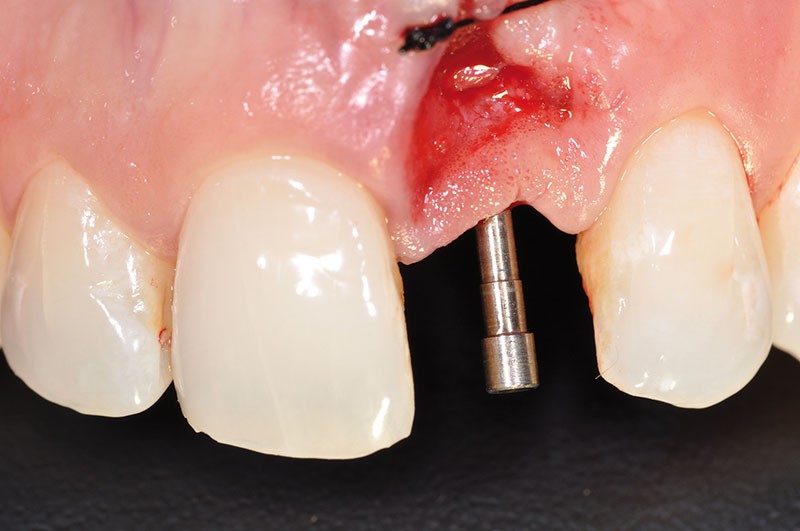

Nous avons choisi de présenter ici un cas d’implantation immédiate après extraction d’une incisive centrale maxillaire gauche (21) associée à la réhabilitation esthétique de son environnement parodontal et péri-implantaire dans ce secteur.

On objective, dans la partie la plus apicale du vestibule, la présence d’une zone infectieuse (abcès parodontal) causée, entre autres, par la forte résorption externe de la racine (fig. 3).